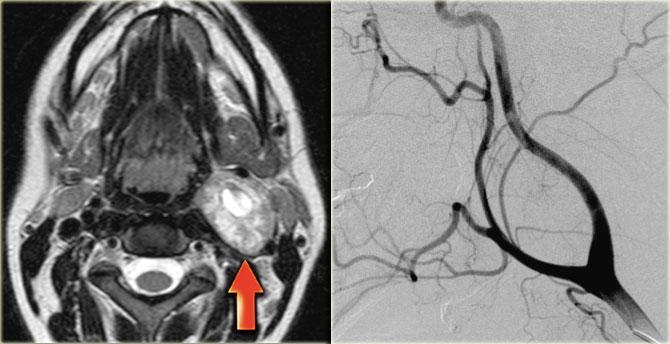

Paraganglioma: Hình ảnh MRI chuỗi xung T1W có tiêm thuốc tương phản từ Gadolinium tại mức thanh quản trên thanh môn

Paraganglioma

Bước 1: Xác định khoang

Bên trái là hình ảnh một bệnh nhân có khối sưng ở bên trái cổ.

Hãy quan sát hình ảnh MRI tại mức thanh quản trên thanh môn và xác định tổn thương nằm trong khoang nào.

Sau đó tiếp tục đọc.

Khối sưng nằm tập trung giữa động mạch cảnh ngoài và động mạch cảnh trong.

Lưu ý rằng các mạch máu này bị chèn ép.

Rõ ràng tổn thương này phải nằm trong khoang cảnh.

Cần lưu ý rằng có một tổn thương nhỏ hơn nhưng có hình thái tương tự, nằm ở khoang cảnh bên phải.

Paraganglioma thường gặp dạng đa ổ ở 3% đến 5% bệnh nhân nói chung và 20% đến 30% ở những người có tiền sử gia đình dương tính.

Các tổn thương này ngấm thuốc mạnh trên CT và MRI như được thấy trên hình ảnh MRI mặt phẳng coronal sau tiêm Gadolinium này.

Trong tổn thương lớn hơn ở bên trái, có thể thấy các vùng mất tín hiệu dòng chảy điển hình (xem thêm hình ảnh mặt cắt ngang).

Vì vậy, chúng ta có thể kết luận rằng có các tổn thương ngấm thuốc mạnh hai bên với hiện tượng mất tín hiệu dòng chảy trong khoang cảnh, nhiều khả năng nhất là u thể cảnh hoặc paraganglioma.